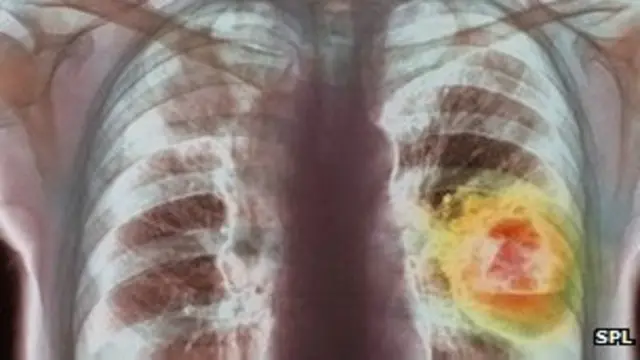

Penelitian yang dilakukan di enam pusat riset itu , akan mencari jawaban bagaimana <link type="page"><caption> kanker paru-paru</caption><url href="http://www.bbc.co.uk/indonesia/majalah/2013/06/130612_iptek_kanker.shtml" platform="highweb"/></link> menjadi kebal terhadap perawatan.

Studi akan melacak bagaimana tumor paru-paru berkembang selama beberapa tahun.

Mutasi sel kanker

Dalam salah satu riset terhadap kanker paru-paru ini, para peneliti akan menganalisa perubahan genetik didalam sel kanker dari ratusan pasien dari mulai proses diagnosa sampai perawatan.